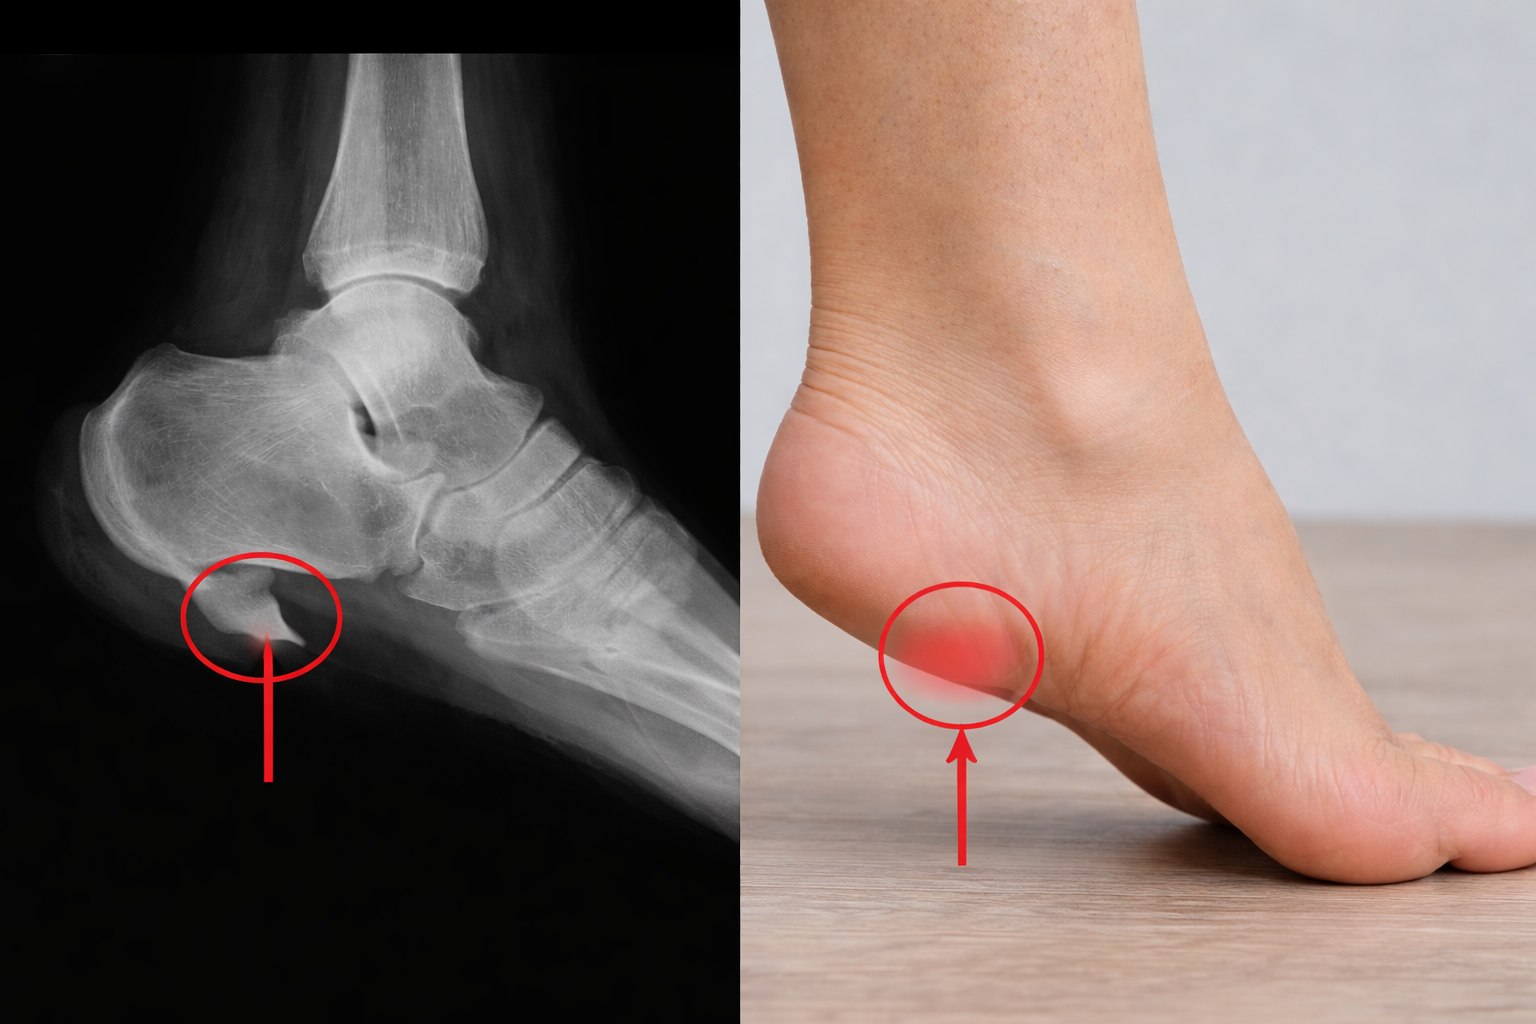

El espolón calcáneo es una alteración muy frecuente en personas que consultan por dolor de talón, pero conviene empezar por una idea clave: no siempre que aparece un espolón en una radiografía es él el verdadero responsable del dolor. En muchos casos, el problema principal está en la fascia plantar, en la sobrecarga mecánica del pie o en una combinación de factores como la rigidez de gemelos, el exceso de impacto o una mala distribución de cargas. Ese es precisamente el punto donde una clínica podológica puede marcar la diferencia: no solo se trata de “ver” el espolón, sino de entender por qué se ha formado y qué estructuras están sufriendo.

El espolón calcáneo es una exostosis o crecimiento óseo que se forma en la zona del calcáneo, habitualmente en la inserción de la fascia plantar. Suele desarrollarse tras un proceso prolongado de tracción, microestrés repetido y adaptación del tejido. Pero aquí está el matiz importante: la presencia del espolón no explica por sí sola los síntomas. De hecho, muchas personas tienen espolón y no sienten dolor, mientras que otras padecen un dolor intenso de talón sin que el espolón sea muy llamativo en imagen.